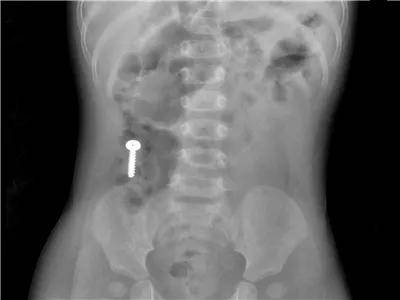

各种年龄误服螺丝钉

这是误服的几个钝头钉,危害相对较小,但看着也很吓人。